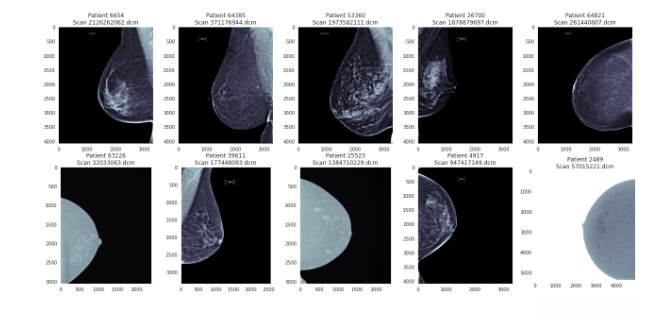

def display_cancer_or_not(cancer=True):

cancer_scans = data[data['cancer'] == int(cancer)].sample(frac=1, random_state=0)

plt.figure(figsize=(22, 10))

for i in range(10):

patient = str(cancer_scans.iloc[i][['patient_id']][0])

file = str(cancer_scans.iloc[i][['image_id']][0]) + '.dcm'

scan = pydicom.dcmread(train_path + '/' + patient + '/' + file)

plt.subplot(2, 5, i+1)

plt.imshow(scan.pixel_array, cmap='bone')

plt.title(f"Patient {patient}\nScan {file}")

plt.grid(False)

plt.suptitle(f"Cancer = {cancer}")

plt.show()

display_cancer_or_not(cancer=True)